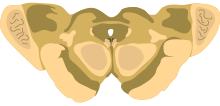

The midbrain is usually sectioned at the level of the superior and inferior colliculi.

- A horizontal (transverse) cross-section at the level of the superior colliculus shows the red nucleus, the nuclei of the oculomotor nerve (and associated Edinger-Westphal nucleus), the cerebral peduncles or crus cerebri, and the substantia nigra.[7]

- A horizontal (transverse) cross-section at the level of the inferior colliculus still shows the substantia nigra. Also apparent are the trochlear nerve nucleus, and the decussation of the superior cerebellar peduncles.[8]

- Both sections will show the cerebral aqueduct, which connects the third and fourth ventricle and the periaqueductal gray.[9]

One mnemonic for remembering the structures of the midbrain involves visualizing the mesencephalic cross-section as an upside down bear face. The two red nuclei are the eyes of the bear and the cerebral crura are the ears. The tectum is the chin and the cerebral peduncles are the face and ears.